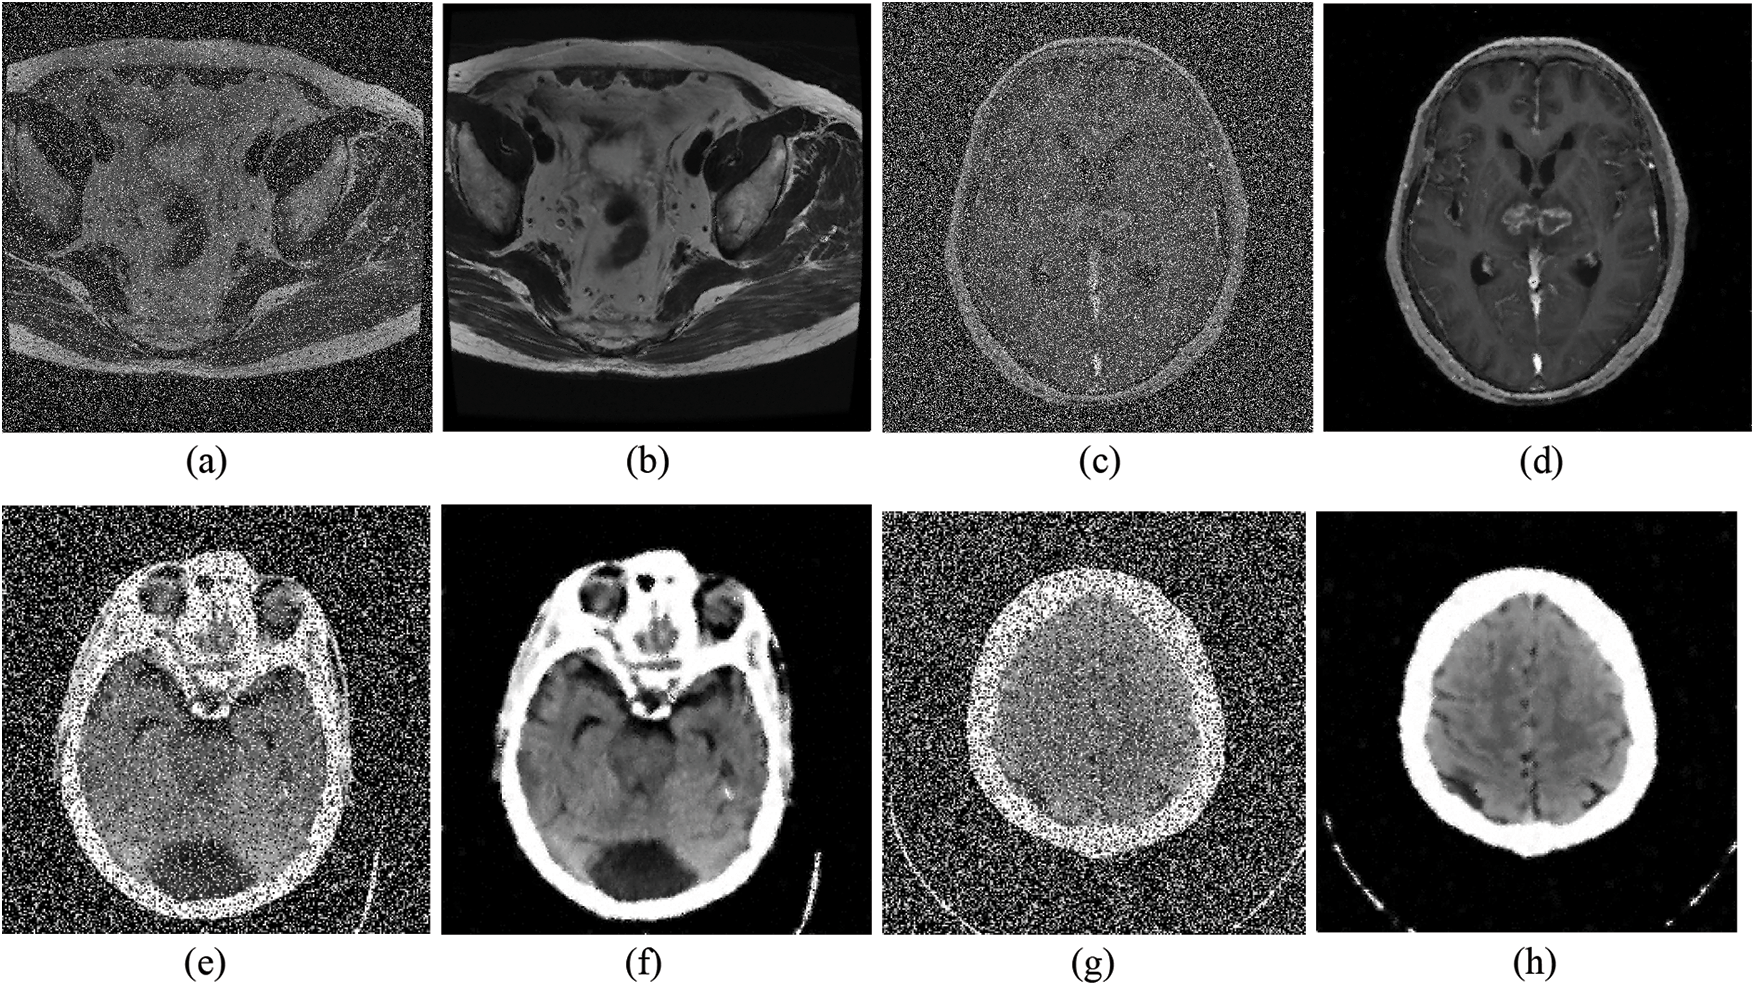

In this section, the noise detection and removal experiments are performed on natural images and medicals image to verify the performance of the proposed method. The test images are shown in Fig. 4, where Figs. 4a–4g are natural images, Figs. 4h–4i are medical images. All image sizes are 512 × 512, except that of the size of House. To quantitatively and qualitatively evaluate the performance and effect of the proposed two-stage denoising algorithm, this paper use the Miss Detected pixels (MD) and False Detected pixels (FD) indexes commonly used in other literature to evaluate the noise detector, and Structural Similarity (SSIM) and Peak Signal to Noise Ratio (PSNR) indexes to evaluate the filter.

Figure 4: The test images: (a) Lena, (b) Peppers, (c) Barbara, (d) Boat, (e) House, (f) Bridge, (g) Baboon, (h) Gehirn, (i) Prostate

5.4 Restoration Performance on Medical Image

Denoising experiments on medical images were conducted as shown in Fig. 8. It can be seen that the denoising algorithm proposed in this paper can restore biomedical images with different textures and resolutions under different levels of RVIN. From the restored medical image, it also can be intuitively observed that the algorithm in this paper also has a good texture and edge preservation ability in a medical image, which helps to ensure the correct diagnosis and treatment in the follow-up. In general image processing, small details have little impact on the subsequent processing procedures of image noise reduction. However, such small mistakes are not allowed when the processing object is medical images, because, in medical diagnosis or treatment, every small mistake will affect the treatment methods and even threaten the life of the patient.

Figure 8: The filtering effects of the proposed method on Prostate and Gehirn noisy images: (a) Prostate with 30% RVIN; (b) restored image of (a), PSNR = 31.82; (c) Gehirn with 50% RVIN; (d) restored image of (c), PSNR = 29.76; (e) Brain with 40% RVIN; (f) restored image of (e), PSNR = 22.47; (g) Cross section of brain with 50% RVIN; (h) restored image of (g), PSNR = 23.26